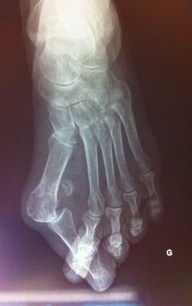

- vos derniers examens médicaux (radios, scanner, IRM…) en rapport avec le motif de consultation, si vous en avez.

Exemples d’indications au port d’orthèses plantaires :

- les hallux valgus, hallux rigidus, toutes les pathologies articulaires (arthrose par exemple),